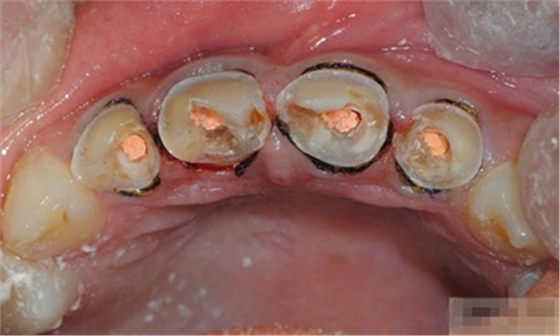

【檢查】12,11,21,22,均行玻璃離子充填,各牙不同程度部分充填物脫落,探(—),叩(—),冷刺激無(wú)反應(yīng),無(wú)松動(dòng),牙齦顏色粉紅,質(zhì)地堅(jiān)實(shí)而有彈性,點(diǎn)彩正常,牙結(jié)石(—);牙髓活力測(cè)試無(wú)反應(yīng)。

【診斷】12,11,21,22牙體缺損

【分層堆塑】

A4本質(zhì)堆塑

A3本質(zhì)堆塑

發(fā)育葉制作

白堊斑

切端琥珀色制作

A3頸部堆塑